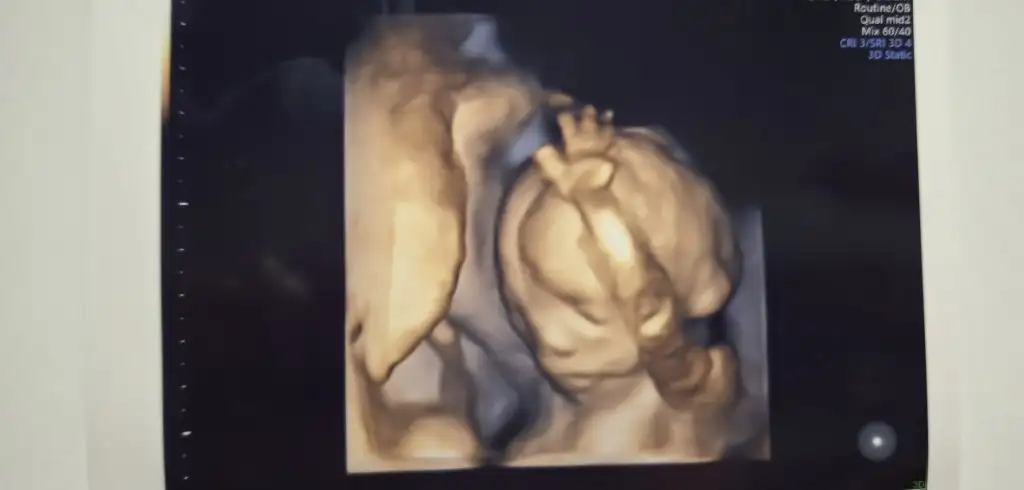

Herkese merhaba bizim de bugün kontrolümüz vardı.Giderken çikolata kahve muz filan yedim hareket etsin diye. Gittiğimizde hareket etmiyordu sonra birden ben burdayim der gibi elini kaldırdı ☺️😂 Bu arada o pıt pıt atışları 14+5 günlükken hisetmeye başladım bence de o hareketler bebek şu an 18. haftadayız özellikle yemekten ve tatlıdan sonra hemen hissediliyor ve ilk bebek olmasına rağmen 😊

Herkese merhaba bizim de bugün kontrolümüz vardı.Giderken çikolata kahve muz filan yedim hareket etsin diye. Gittiğimizde hareket etmiyordu sonra birden ben burdayim der gibi elini kaldırdı ☺️😂 Bu arada o pıt pıt atışları 14+5 günlükken hisetmeye başladım bence de o hareketler bebek şu an 18. haftadayız özellikle yemekten ve tatlıdan sonra hemen hissediliyor ve ilk bebek olmasına rağmen 😊Eki Görüntüle 3459277